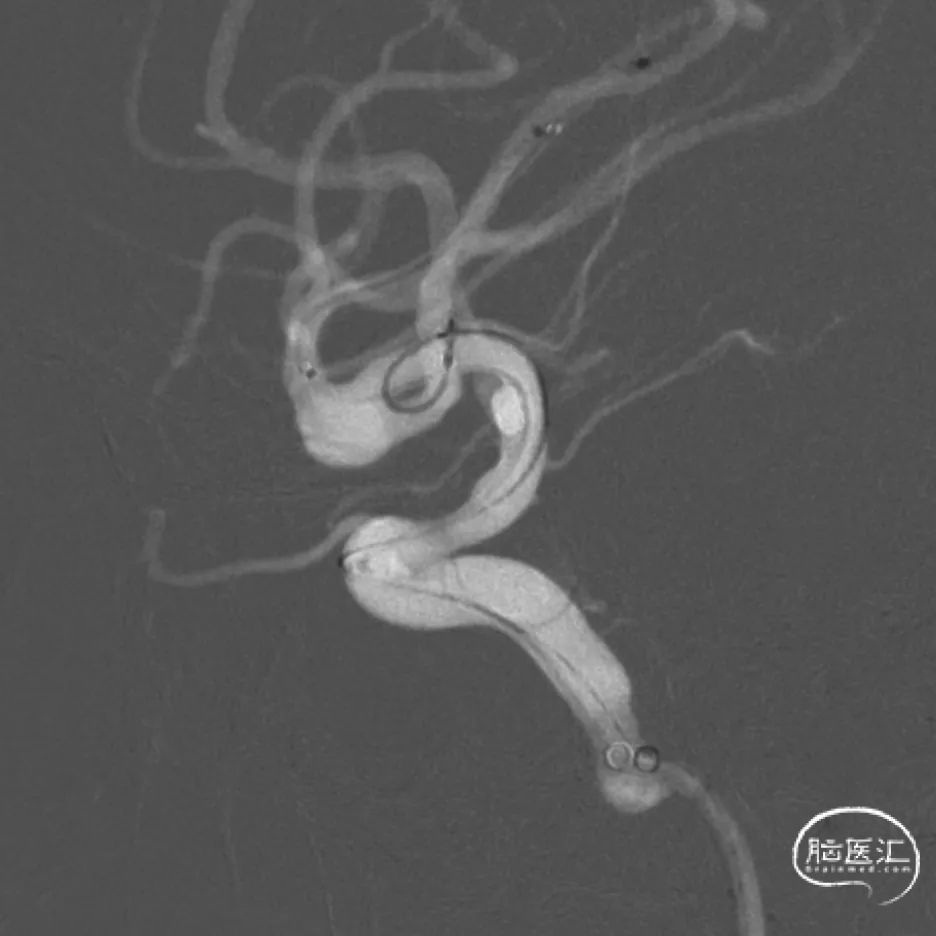

经下干的SL-10微导管释放第二枚Atlas支架,形成“Y”型支架形态,充分保护上下两干,Atlas支架打开顺畅,影像下可清晰看到两端标记点完全打开。第二枚支架释放完毕后,顺势将该SL-10微导管经支架网眼顺利超选入瘤腔,拟双微管填塞。经一根SL-10微导管释放第一枚Target XL 4mm*12cm弹簧圈进行成篮。

相继填入Target系列弹簧圈,型号分别为2mm*8cm、2mm*6cm(两枚)、1.5mm*4cm(两枚)。

术后即刻工作位造影及蒙片:

术后即刻正位造影及蒙片:造影显示瘤体致密栓塞,支架贴壁和导流良好。